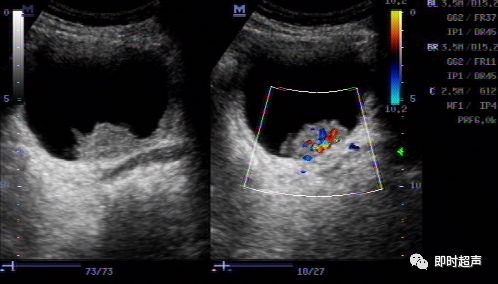

典型膀胱癌声像图一例

超声入门贴41-----膀胱癌

超声入门贴41膀胱癌